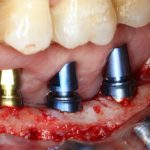

Напомню, что для этой работы я выбрал субкрестальные имплантаты Ankylos C/X. Они прекрасно сочетаются с любым методом остеопластики.

Я не планирую установку супраструктур или коронок, поэтому на уровень первичной стабильности можно положить болт. Даже наоборот — чем меньше крутящий момент при установке, тем лучше. Для имплантатов Ankylos и подобных им, это особенно важно. В общем, момент силы при установке — не более 10-15 Нсм.

Ремарка: имплантаты с предустановленными имплантодержателями хороши тем, что с ними легко контролировать позиционирование имплантатов. В случае с Ankylos С/Х - еще и крутящий момент. Имплантодержатель должен отсоединяться от имплантата с легким щелчком. Если его клинит, и тебе приходится прикладывать для этого усилия, то ты, однозначно, превысил момент силы во время установки имплантата. Следовательно, жди проблем.

Глянем на то, что получилось:

Осталось адаптировать костный блок (убрать острые края), проверить его фиксацию и, при необходимости, добавить винты. Десятисекундное дело.